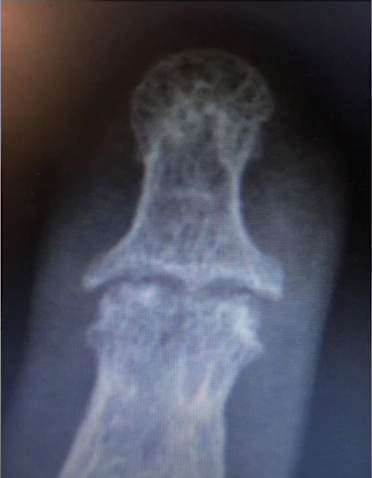

Osteoartrite

Sinal da gaivota

Erosão óssea